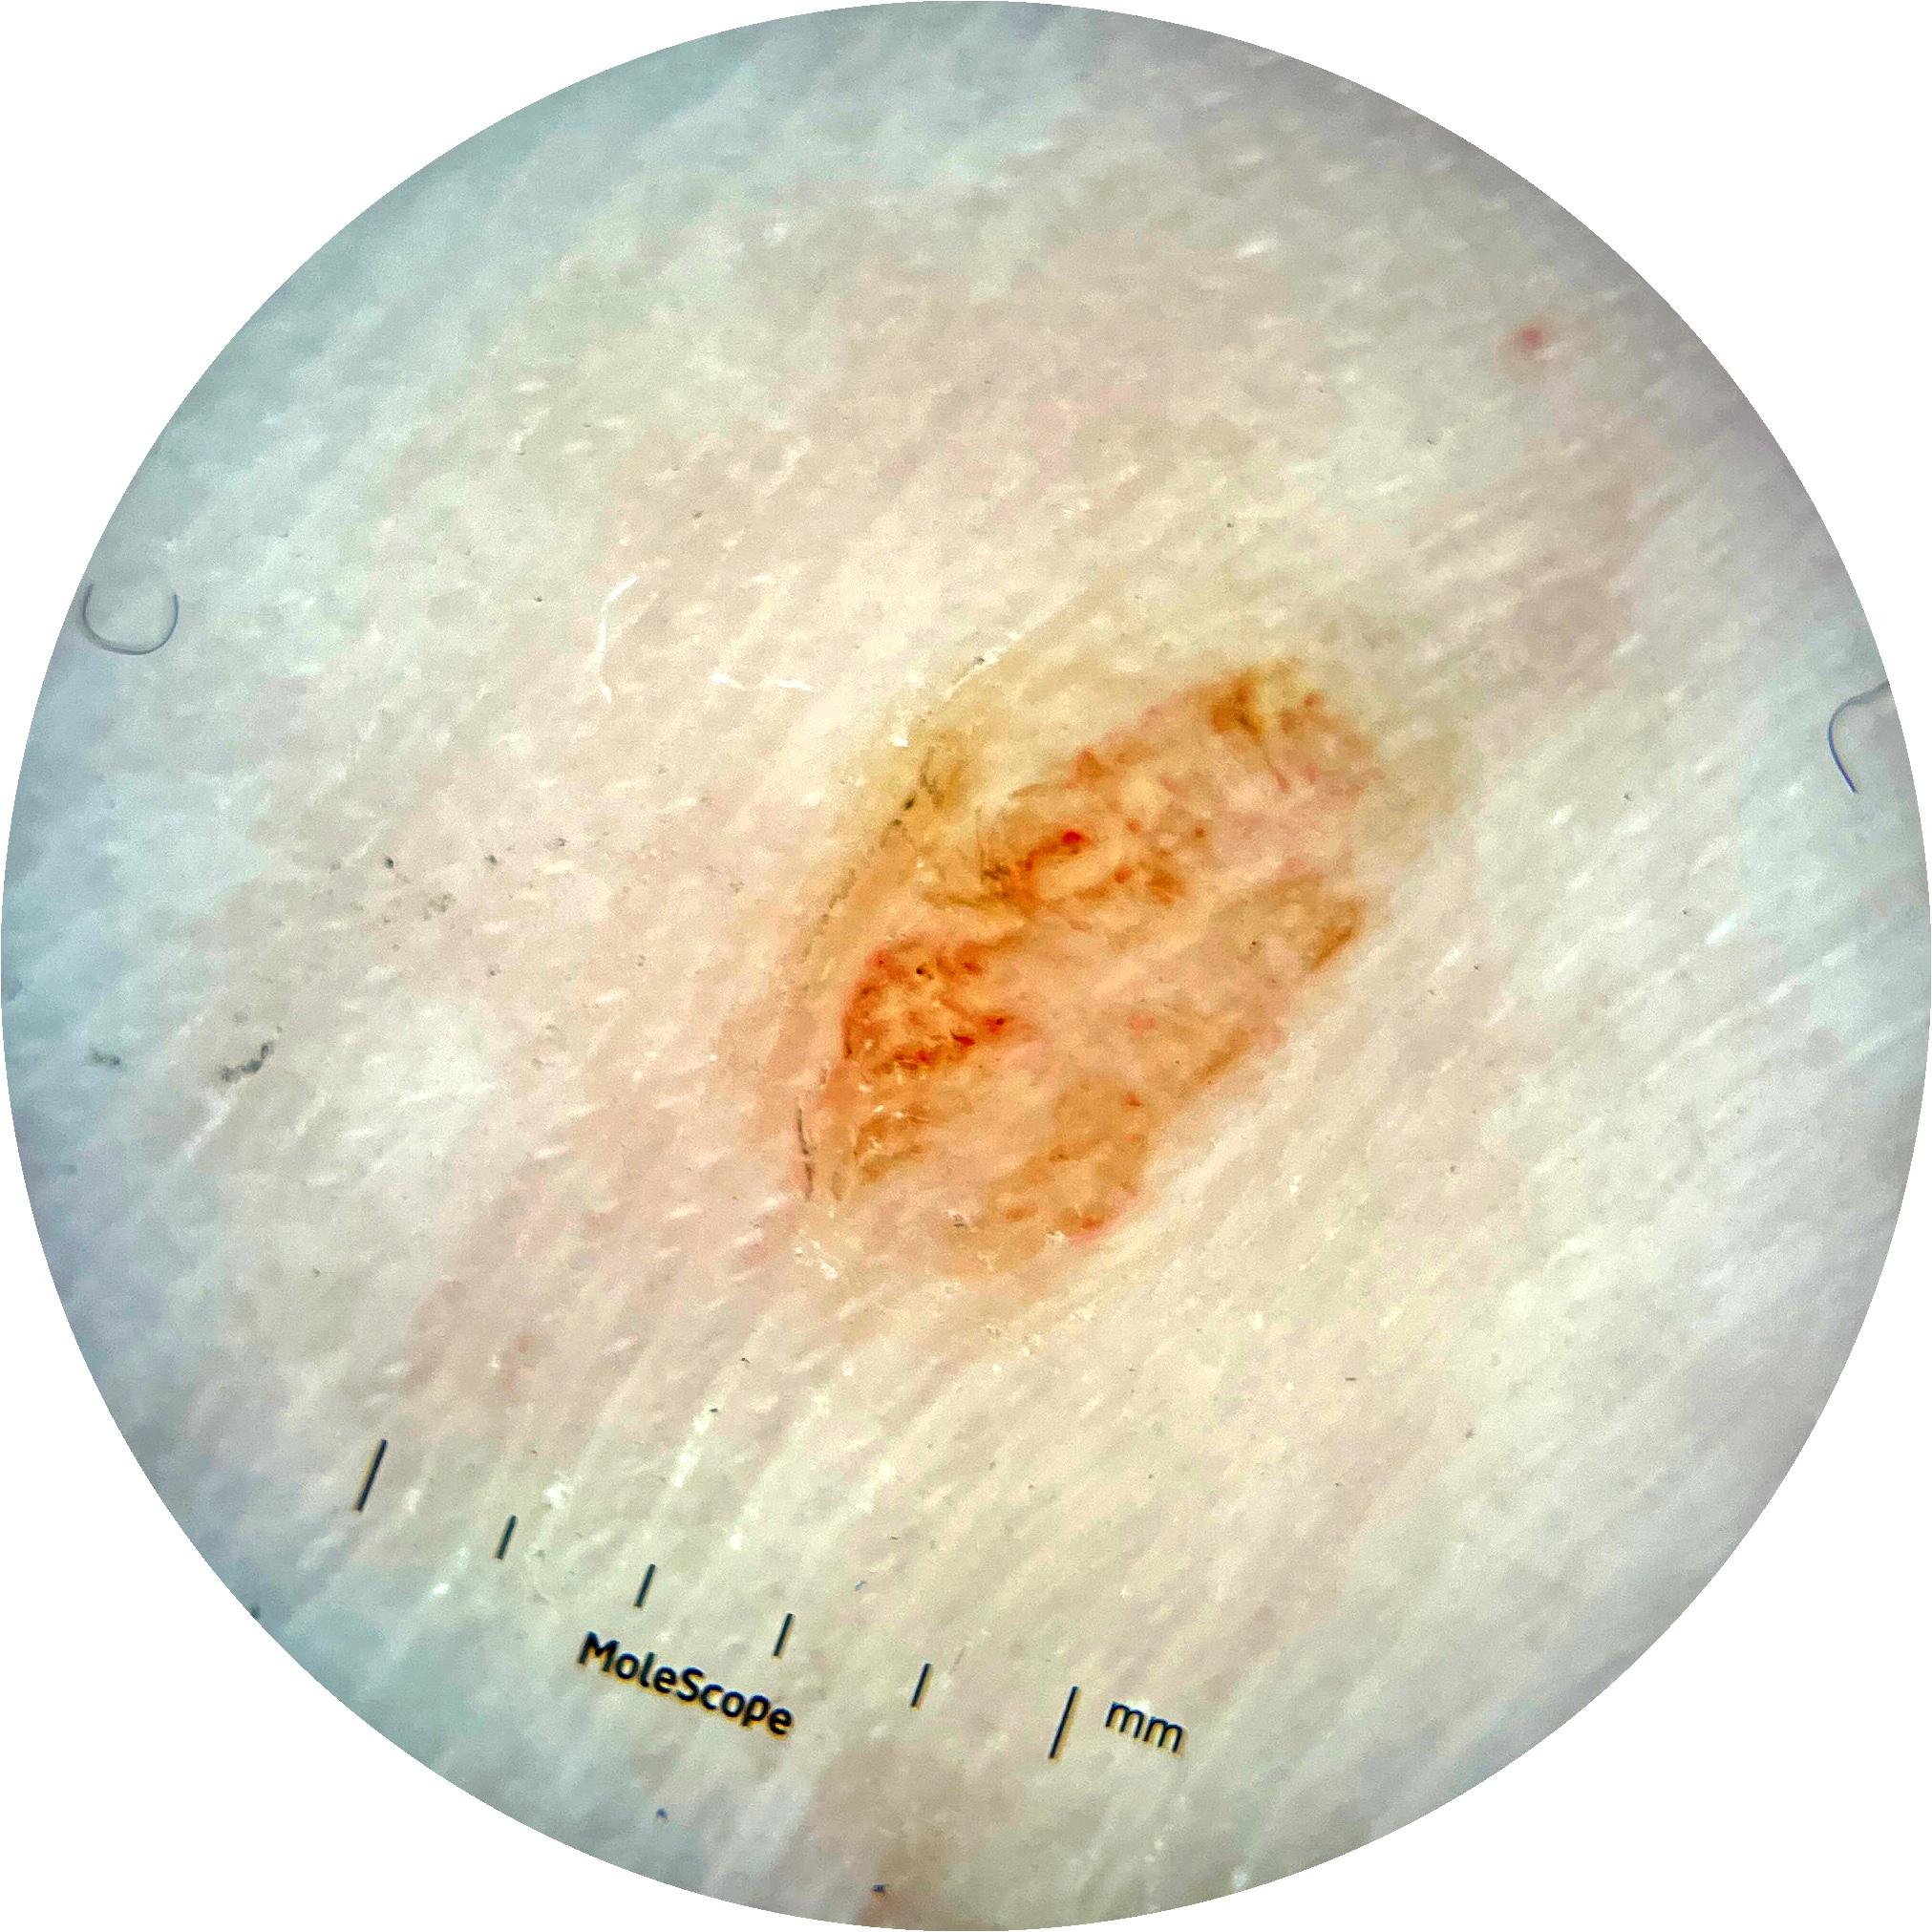

Clinical

Field Value

acquisition_day 341

age_approx 50

anatom_site_1 Lower extremity

anatom_site_general lower extremity

concomitant_biopsy False

diagnosis_1 Benign

diagnosis_confirm_type single image expert consensus

family_hx_mm False

image_manipulation instrument only

image_type dermoscopic

lesion_id IL_9516432

patient_id IP_4450661

personal_hx_mm True

sex male